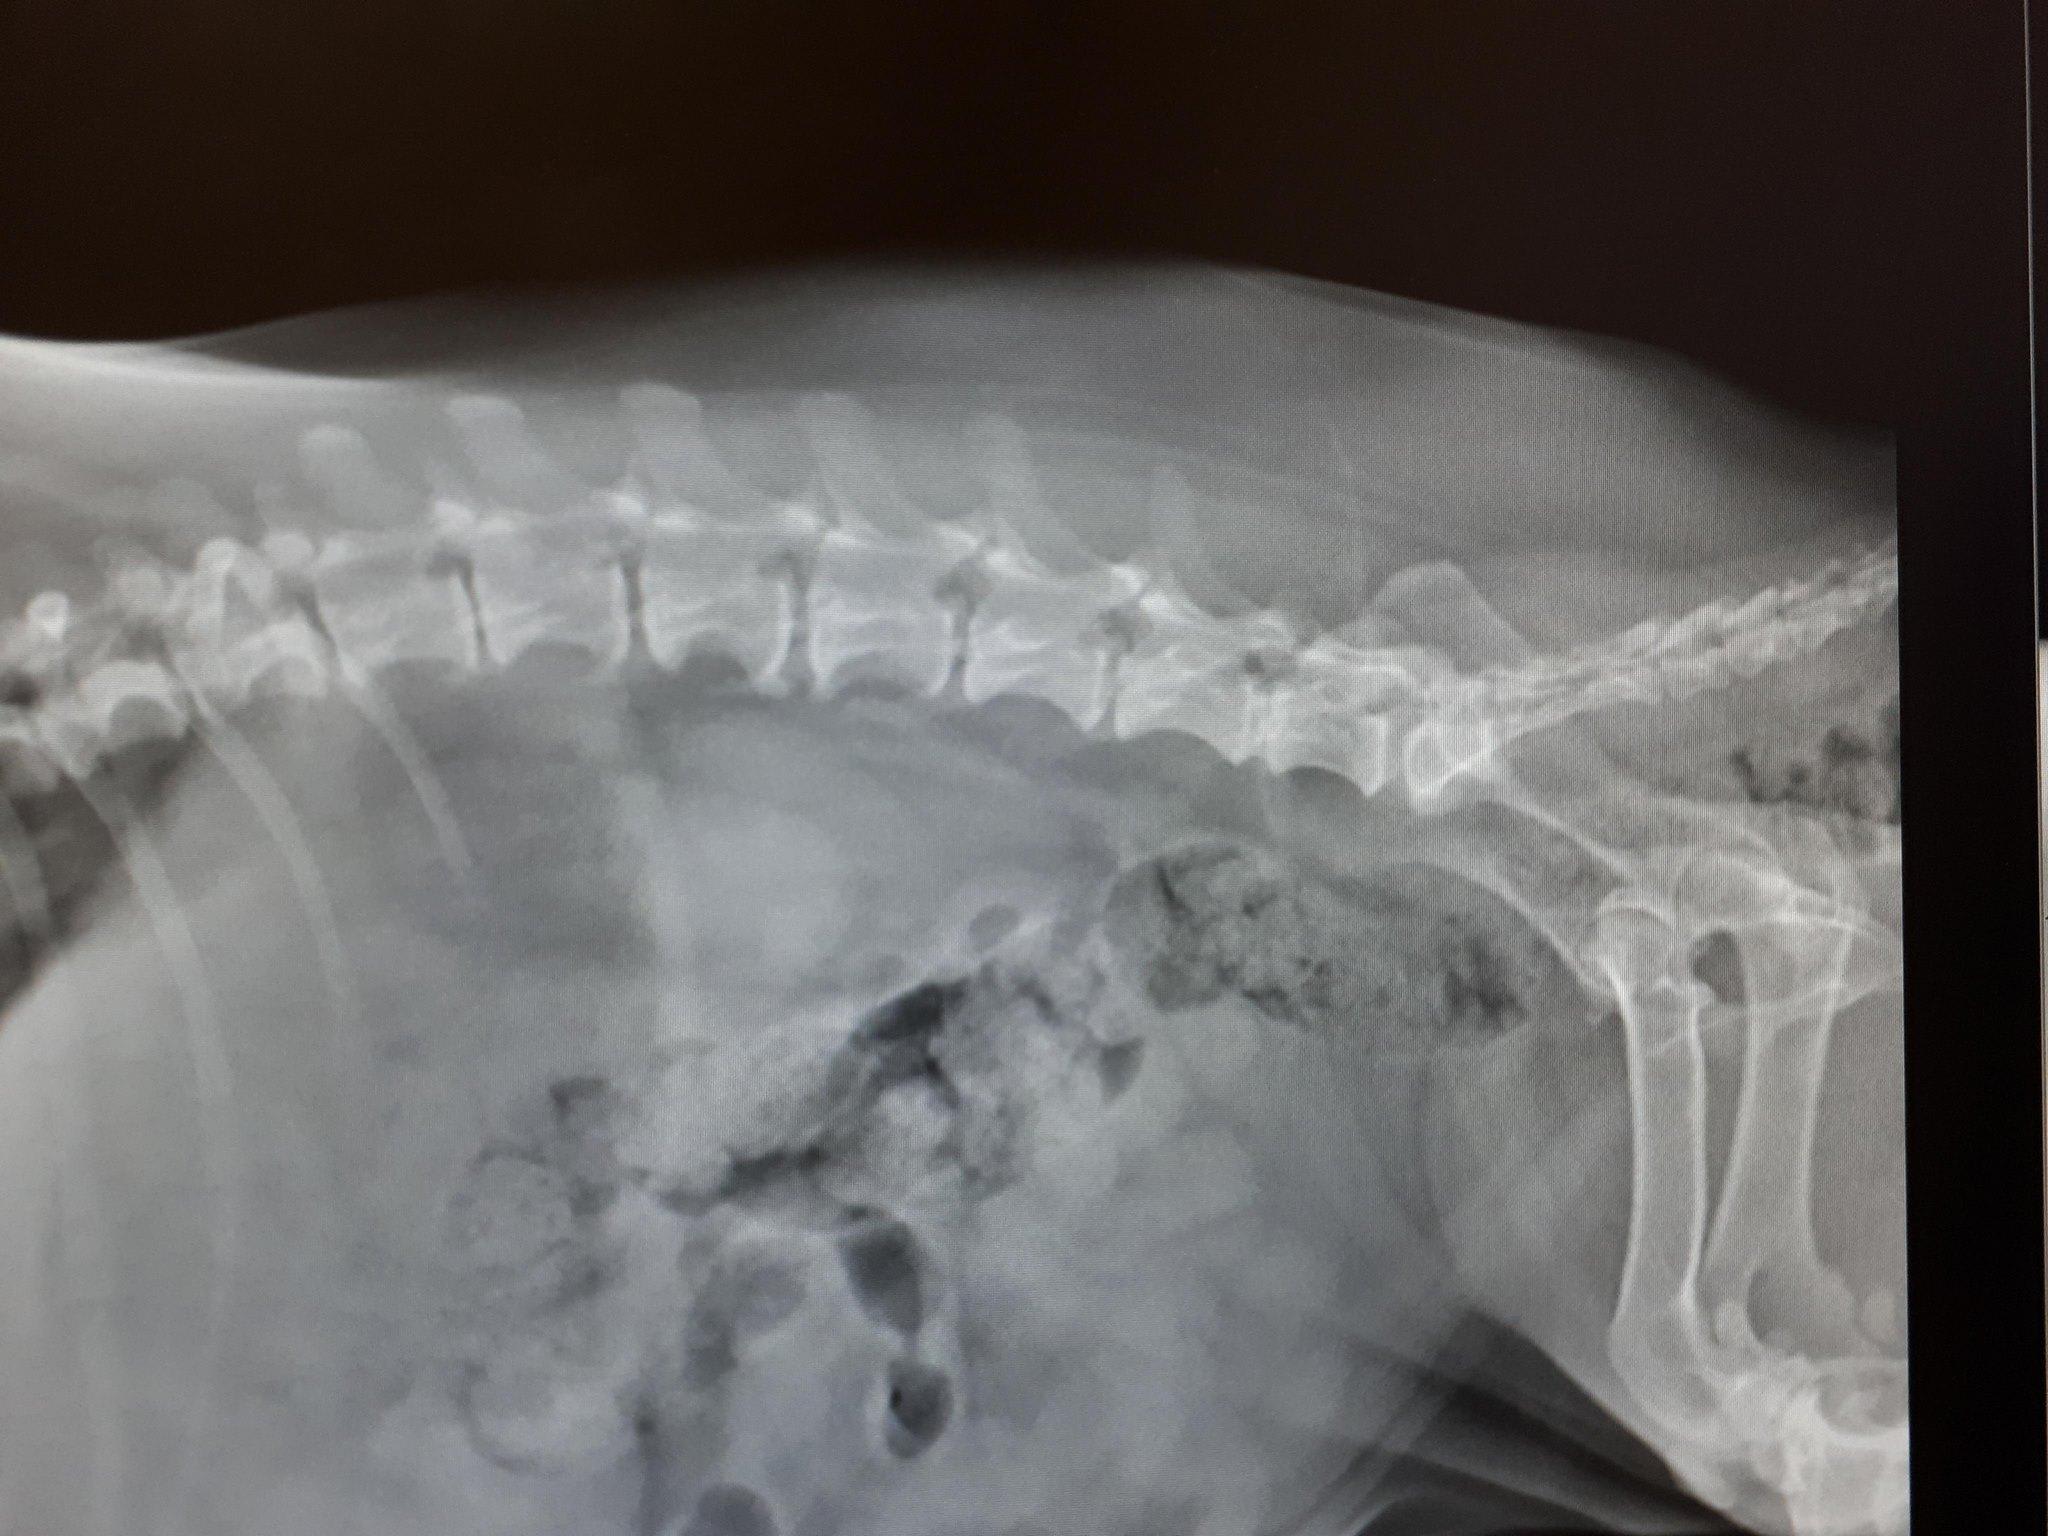

Hello, I just went to my local Animal hospital for my Dachshund, She just lost feeling in her back legs and is unable to walk now. The vet I went to was unable to give me any answers. I was just told to give my dog Prednisone 5mg, 1 tablet twice daily for 5 days, and if effective then 1 tablet daily there after.. The vet told me to just wait and see if this helps the dog.. I have a photo of the x-ray the vet took of my dog, If a vet doctor could please have a look at this. Thank you so much

Hi, thanks for using Petcoach! Poor Emmy! If Emmy lost the feeling in her back legs you should consider taking her to a specialty hospital to have an MRI done and see if she is a candidate for back surgery. There is a fine line with spinal trauma for the dog to be able to regain feeling and the ability to walk again. It is expensive but time is of the essence. If you would do surgery on her you should take her now. Based on the X-ray she may have a mineralized disk L6-L7 but they do not have to be visible on X-ray to be causing the problem. This condition is called Intervertebral-Disk disease and is very common is Dachshunds. https://www.veterinarypartner.com/Content.plx?P=A&S=0&C=0&A=3223 I hope this helps and I wish Emmy the best!